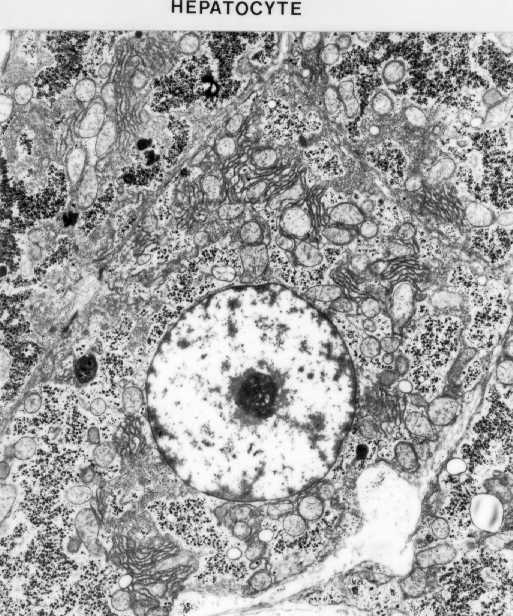

Hepatocyte. Identify its nucleus, nucleolus, chromatin clumps, glycogen masses (dark masses), mitochondria and rER.